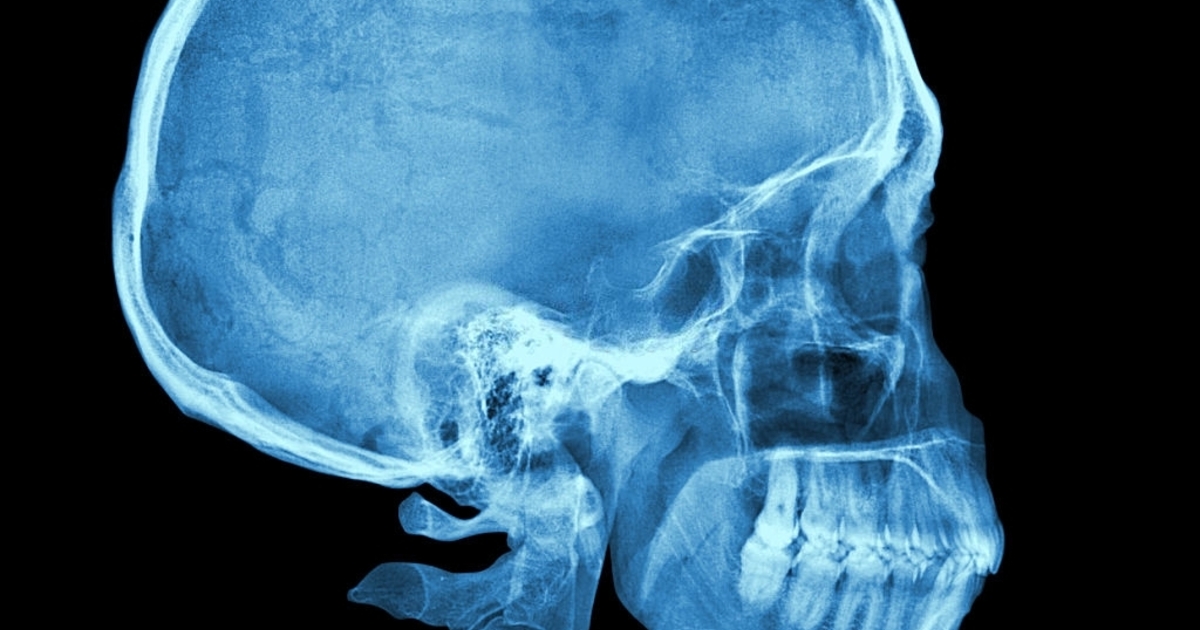

В челюсти человека обнаружили новый слой

Швейцарские учёные обнаружили третий, ранее неизвестный слой в жевательной мышце челюсти человека. Теперь придётся переписывать учебники анатомии.

Ранее считалось, что эта мышца состоит из двух слоёв: поверхностного и глубокого. Учёные обнаружили третий слой, когда изучали более двух десятков человеческих голов. 12 из них были заспиртованы ранее. В итоге исследователи увидели, что один глубокий участок жевательной мышцы чётко отличается от двух других слоев с точки зрения его функций.

Третий слой мышца назвали «короноидным» (Musculus masseter pars coronidea). Выяснилось, что он участвует в поддержании стабильности челюсти и может быть единственным, кто отвечает за подтягивание её нижней части к уху. Этот слой проходит от задней части скулы до переднего мышечного отростка нижней челюсти.